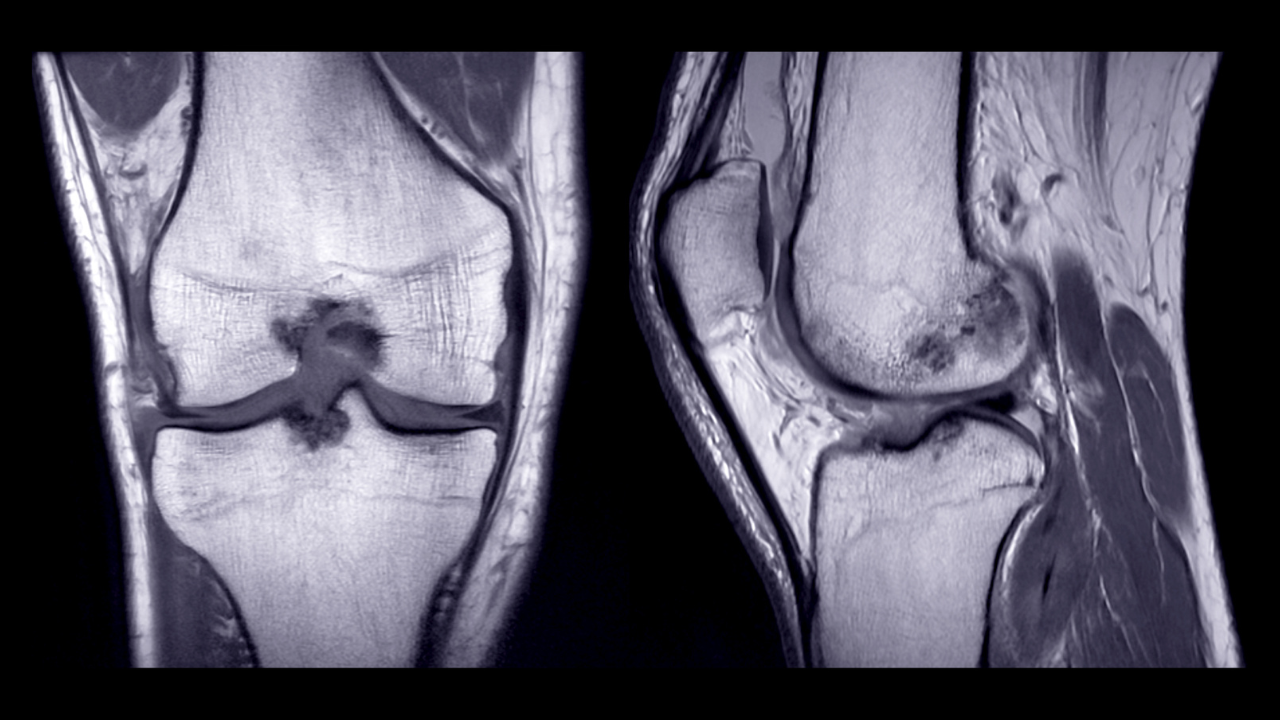

Imaging for Meniscal Tears

Imaging is sometimes used to clarify the diagnosis, particularly when symptoms are severe or not progressing as expected.

MRI is the most sensitive investigation for detecting meniscal tears because it allows direct visualisation of the cartilage structures within the knee. It can also identify associated findings such as ligament injury, cartilage damage or bone stress response.

However, MRI findings must always be interpreted alongside clinical examination. Many people have meniscal changes on scan that are not responsible for their symptoms.